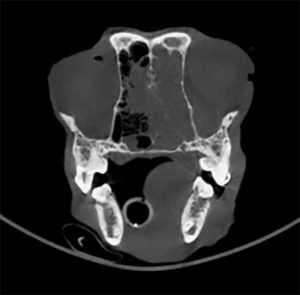

Cone-beam CT scan shows a predominantly left-sided nasal tumor that extends into the olfactory lobe of the patient's brain.

My first comment on hearing about the nosebleed was, "We may have found our primary site of carcinoma." Around the same time as the onset of epistaxis, Dante's mentation quickly progressed to a much more dull state when compared to a relatively normal level of lucidity when he arrived at our hospital. We discussed our concerns with Dante's mom, and she agreed diagnostics were warranted to assess the nose for possible primary nasal carcinoma. We placed Dante under anesthesia and performed a cone-beam computed tomography (CBCT) scan that revealed an aggressive nasal tumor filling the entire left nasal passage and causing lysis of the cribriform plate, extending into the olfactory lobe of the brain. After showing Dante's mom the CBCT and discussing the options, she decided to not pursue radiation/chemotherapy. Her primary concern was preventing Dante from suffering further, and she requested we euthanize him while he was still under anesthesia.